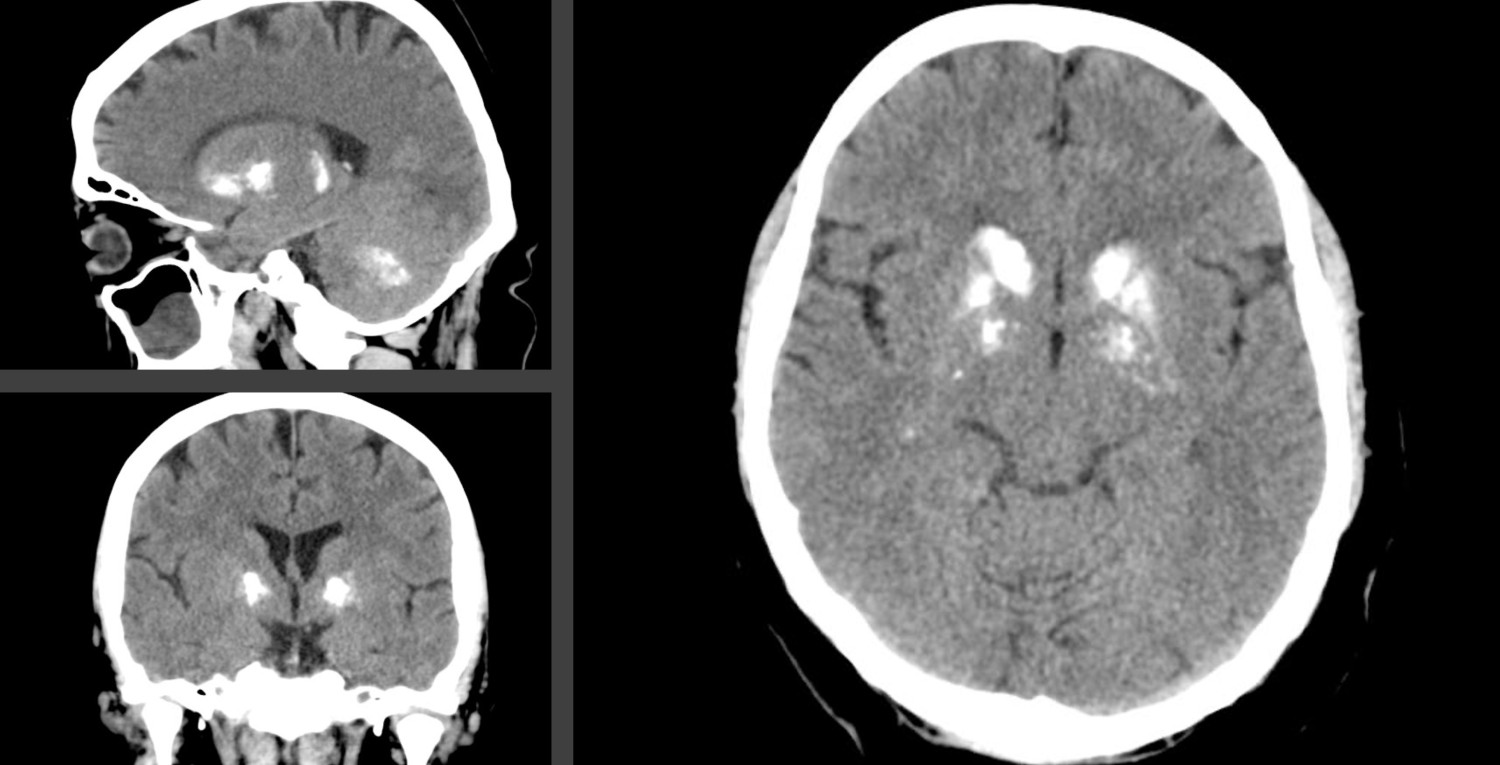

Fahr's disease is a genetic condition characterised by dystonia, ataxia, parkinsonism and various neuropsychiatric symptoms, caused by symmetrical calcifications in the brain (Figure 1). Symptoms and clinical findings can range from minimal to life-threatening (1). There is currently no effective treatment for this progressive disease, but the latest research shows several medicinal avenues (2). Some studies also suggest that the condition may be more widespread than previously thought (3, 4). This brings up questions about what the disease should be called in Norwegian.

Fahr's disease has often been referred to as idiopathic basal ganglia calcification, i.e. calcifications located in the basal ganglia without a known cause. This term is a good description of the anatomical location of the calcifications, but the word 'idiopathic' is no longer adequate as the condition has now been shown to have a genetic cause. Furthermore, the calcifications can also occur in other areas of the brain, such as the subcortical white matter, thalamus and cerebellum (8).